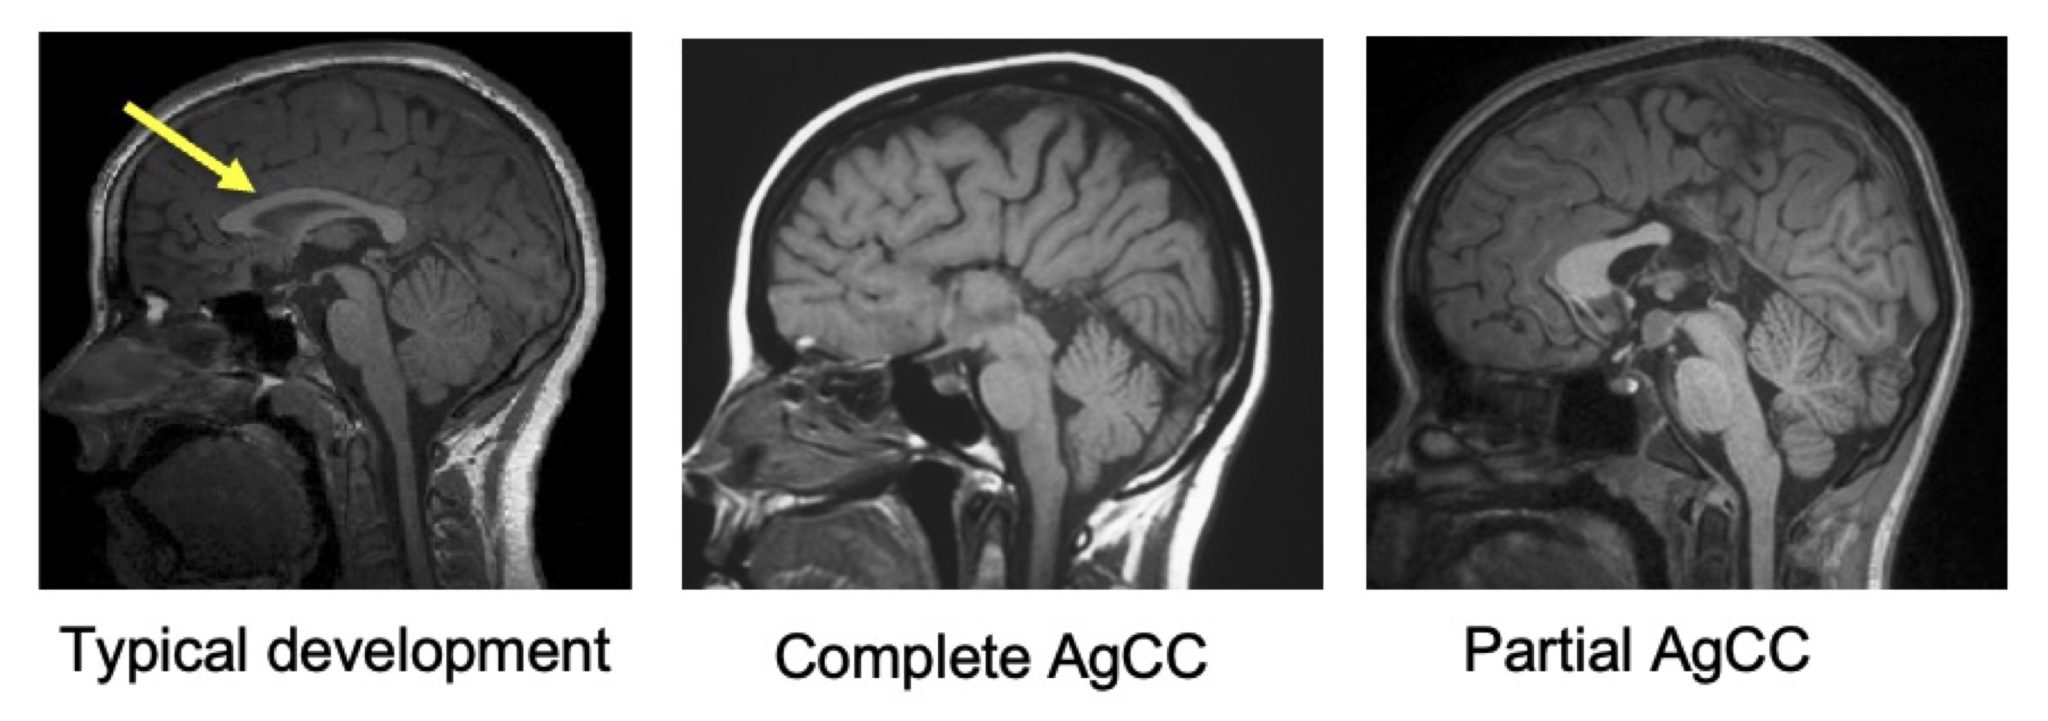

Figure. T1-weighted, sagittal slice, of typically developing children, children with complete agenesis of the corpus callosum (AgCC) and partial AgCC. The corpus callosum is indicated with a yellow arrow in the typical development case.

The corpus callosum is the largest white matter structure in the human brain, containing over 190 million axons that connect the left and right hemispheres. A developmental absence of this structure—known as agenesis of the corpus callosum (AgCC)—is one the most common congenital brain malformation (see Figure). AgCC can result in either complete or partial absence of the corpus callosum and is associated with variable cognitive, behavioral, and neurological outcomes. Diffusion-weighted imaging enables the in vivo reconstruction of white matter pathways. This neuroimaging tool is particularly well suited for studying populations with abnormalities of white-matter development —such as AgCC—as it enables the exploration of potential structural neuroplastic responses in such atypically developing brains. Despite its clinical relevance, research in this area remains limited, largely due to the rarity of the condition. A pioneering study by Bénézit et al. (2015) explored white matter reorganization in a small sample (n = 6, https://doi.org/10.1016/j.cortex.2014.08.022).